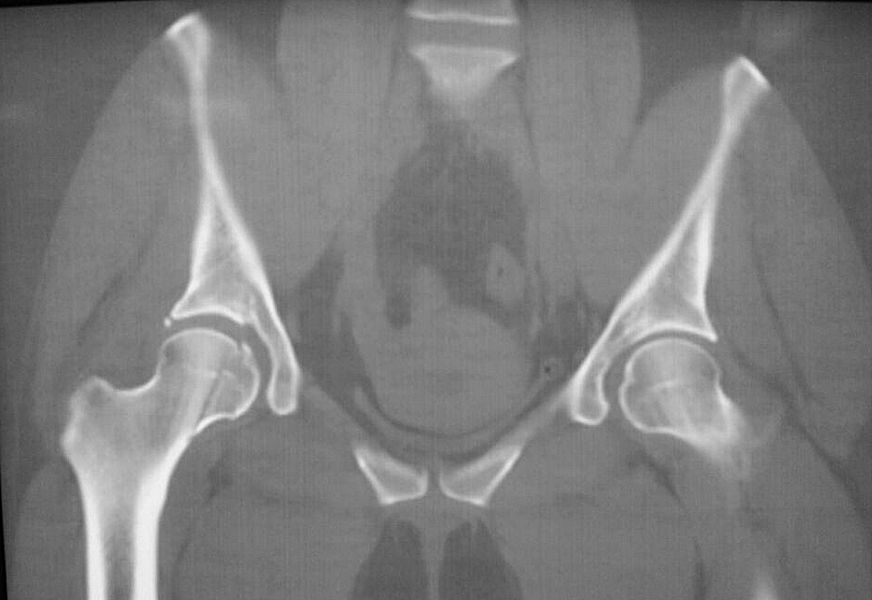

За праздники поступил еще один Pipkin IV. Женщина 30 лет, пострадала в ДТП

(пассажир). Сочетанная травма (ISS 25). Множественные переломы ребер с двух

сторон с пневмотораксом  и пневмомедиастинумом. Закрытый перелом пилона

справа. Задний переломо-вывих головки правой бедренной кости (Pipkin IV).

правой нижней конечности в день поступления. КТ контроль показал довольно

сносную картину результата репозиции. Отломок головки оставался в полости

сустава во время вывиха, т.к. видимо сохранилось прикрепление со связкой.

На КТ остается широкой суставная щель, что косвенно может указывать на

интерпозицию мягкими тканями, либо "встать на место" мешает медиальный

отломок головки.